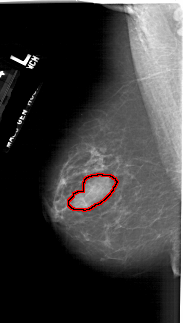

A_1740_1.LEFT_MLO

FILE: A_1740_1.LEFT_MLO.OVERLAY

TOTAL_ABNORMALITIES 1

ABNORMALITY 1

LESION_TYPE CALCIFICATION TYPE PLEOMORPHIC DISTRIBUTION CLUSTERED

ASSESSMENT 4

SUBTLETY 5

PATHOLOGY BENIGN_WITHOUT_CALLBACK

TOTAL_OUTLINES 1

BOUNDARY